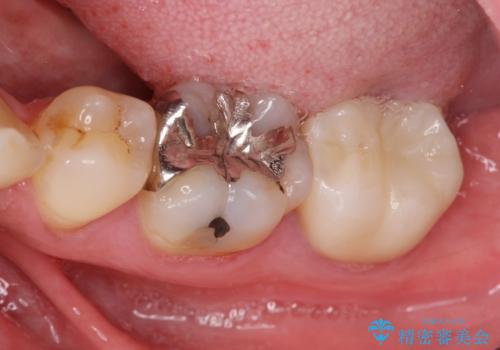

[ 金属アレルギー ] 銀歯を除去するメタルフリー治療

担当医 大元洋佑